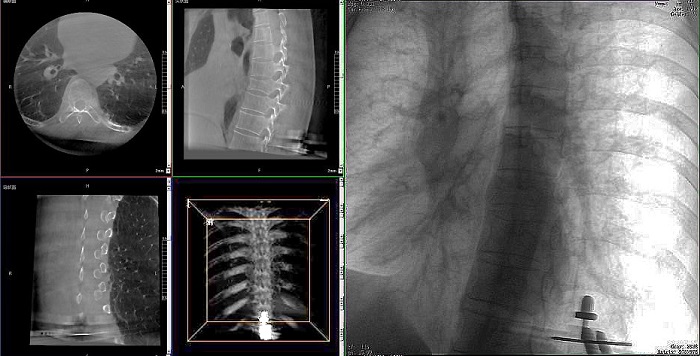

①机器人辅助胸椎手术操作难点之图像采集

胸椎紧邻肺部,患者的呼吸运动会造成椎节的相对移动,获取清晰、稳定的影像较为困难。高质量的影像是精准导航的重要前提,胸椎手术中,如果呼吸造成的移动无法得到有效控制,则会降低导航的精度,增加手术风险。人体深吸气胸围与深呼气胸围的差值约为6~8厘米。

高清三维成像:普爱医疗精研三维成像技术13年,自研的三维C形臂可为手术提供清晰、稳定的三维图像,为医生精准开展胸椎手术提供影像保障。

快速扫描:麻醉师通过适当的呼吸控制,配合三维C形臂的快速扫描模式,可以在短时间内完成图像采集,减少因呼吸运动造成的图像干扰。